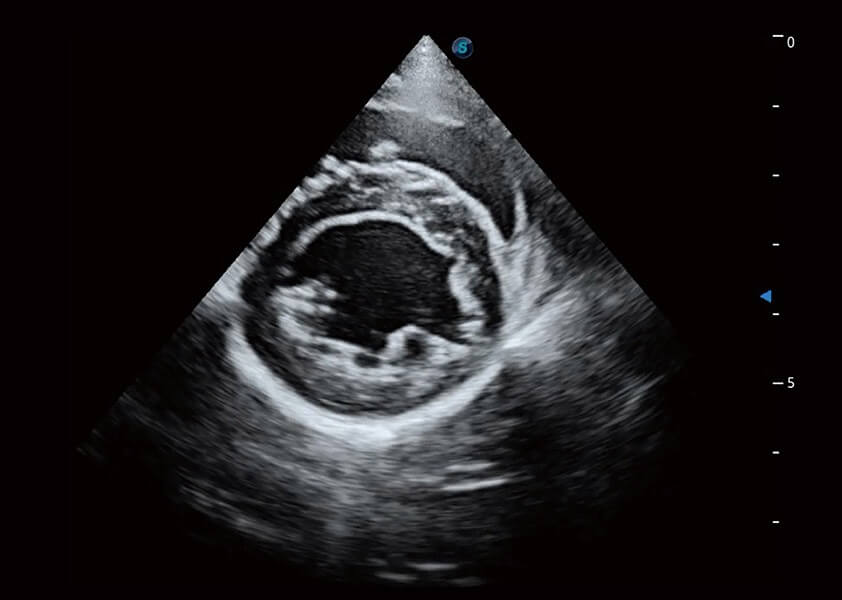

ProPet 60 作為一款高端臺(tái)式動(dòng)物超聲設(shè)備,為動(dòng)物醫(yī)生的日常診斷提供了一系列貼合動(dòng)物臨床需求、解決臨床實(shí)際問題的高級(jí)成像功能。憑借全系列高清探頭,滿足醫(yī)生對(duì)腹部、心臟、生殖、淺表、肌骨等成像的所有需求,切實(shí)幫助您提升檢查效率,提高診斷信心。